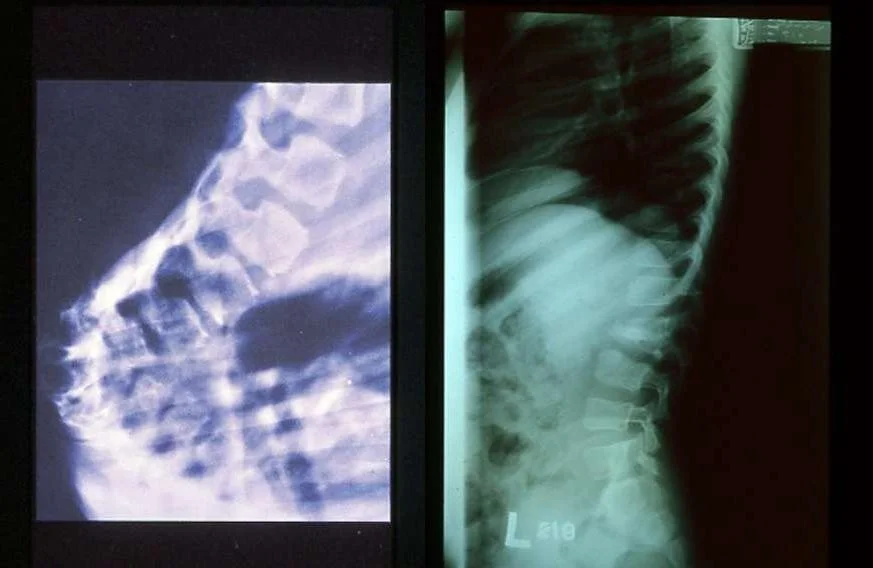

Spinal T.B (Pott’s Disease):

Secondary to hematogenous spread

Affect two or more adjacent vertebrae

Skip levels

Primarily does not affect the disc but eventually the disc is affected

Affects most commonly the anterior part of the vertebral endplates

Causing erosion and destruction and finally anterior wedging of the vertebrae

Infection spreads to adjacent level under the longitudinal ligaments and hematologically

The disc herniates into the weakened and destructed body and narrowing of the disc height follows

Eventually a kyphotic deformity occurs

Para vertebral abscess is common and may be distant as well

- Cervical > retropharyngeal abscess

- Lumbar > psoas abscess

Compression of the spinal cord is more likely to occur at the thoracic level

Neurological deficits occur due to the compression secondary to the deformity or compression from the abscess

Paraplegia may occur